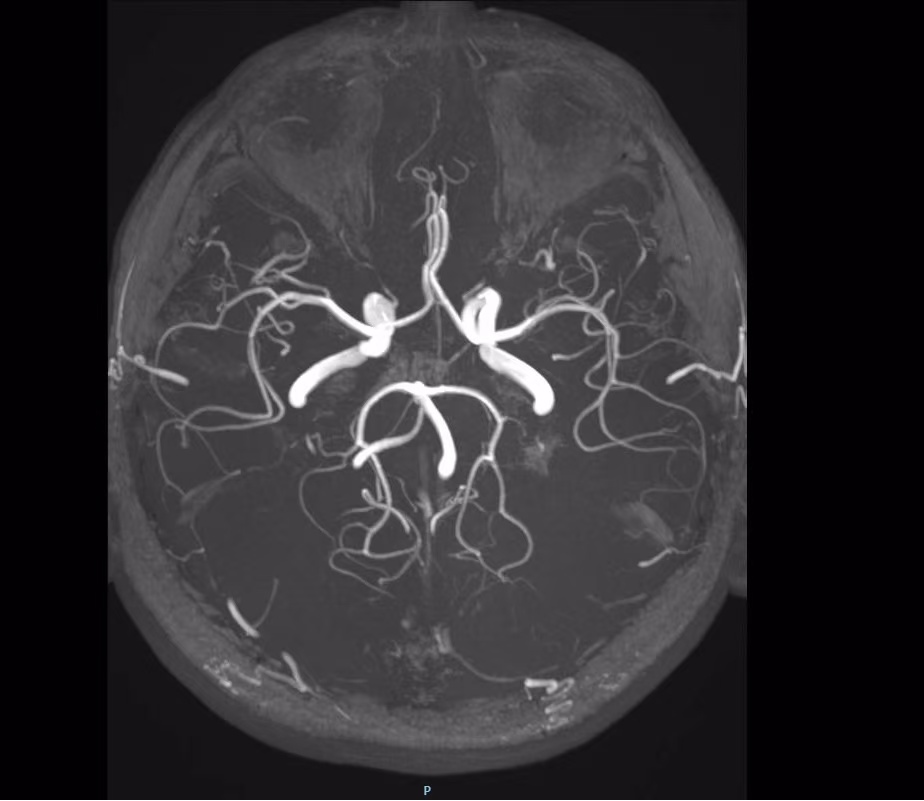

颈椎两侧,人体之上,各有一条位于此处的椎动脉。椎动脉穿行,于颈椎横突孔所构成的,这般的骨性通道之中。其穿行状态恰似,如同穿过隧道的光纤一样。这段存在的解剖结构,致使其活动空间受限。当颈部出现过度活动情况的时候,动脉容易被挤压。椎动脉的职责是负责大脑后循环供血,一旦椎动脉出现受损状况,将直接对脑干功能产生影响。

椎动脉管壁,分为三层构造,中层是由弹性纤维组成的。当碰到超出耐受范围的牵拉力时,内膜会出现撕裂。血液在血压推动下,涌入血管壁夹层,形成血肿,在此过程中,血管壁会如同墙皮剥落一样,层层分离,最终致使管腔狭窄或者闭塞。

视觉障碍呈现为视野缺损又或者视物重影,致使如此的根源是脑干动眼神经核缺血,行走不稳意味着小脑被累及,患者存在突然没办法走直线的可能性,要是出现单侧肢体麻木,亦或者面部感觉异常,这表明感觉神经通路已然受损,必须马上就医。